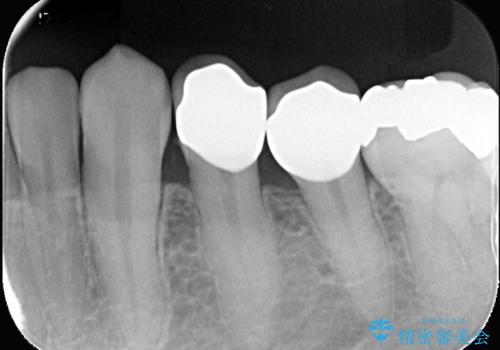

- CRが劣化し欠けてしまっている状態でした。 虫歯を除去後、歯を破折から守るためオールセラミッククラウンで治療を行いました。

- 税込264,000円(オールセラミッククラウン121,000円×2本+仮歯11,000円×2本)費用は治療当時の料金となります

CRが欠けてしまっていて食べ物が凄く詰まる状態でした。

オールセラミッククラウンで治療後、お痛みや食べ物も詰まることなく経過は良好です。